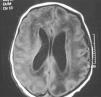

En la bioquímica se observaron 243 U/l de aminotransferasa glutamicoxalacética (GOT), 218 U/l de aminotransferasa glutámico pirúvica (GPT) y 258 U/l de gammaglutamil transpeptidasa. El estudio de coagulación fue normal. La ECO cerebral mostró ventriculomegalia leve, un parénquima cerebral hiperecogénico y vasculopatía de las arterias tálamo-estriadas. No hubo signos de hemorragia. La RM cerebral mostró ventriculomegalia y alteración difusa de la señal en sustancia blanca (fig. 2). El electroencefalograma mostró un trazado normal. La ECO abdominal mostró hepatoesplenomegalia homogénea. El electrocardiograma y la ecocardiografía fueron normales. Se realizó serología para sífilis, toxoplasma, VIH y parvovirus que resultó negativa y serología para CMV, IgM e IgG, que resultó positiva. La punción lumbar fue de 15×106 cél/l, la glucosa fue de 61 mg/dl, las proteínas fueron de 90 mg/dl. El cultivo de orina a los 7 días de vida fue positivo para CMV. La PCR para CMV en sangre y el líquido cefalorraquídeo fueron positivos. El fondo de ojo fue normal. Los potenciales evocados auditivos mostraron ausencia de respuesta a >110 dB en el oído izquierdo (OI) y normalidad en oído derecho (OD). En el primer día y en el tercer día de vida, la niña precisó transfusión de plaquetas, y requirió alimentación por sonda nasogástrica hasta el octavo día. También se inició ventilación no invasiva (presión positiva continua en la vía respiratoria nasal) hasta la semana de vida por pausas de apnea con bradicardia. Se decide no iniciar tratamiento con ganciclovir al considerar que no mejoraba el pronóstico de su enfermedad y por presentar importantes efectos secundarios. Se le da de alta a los 15 días de vida.

Figura 2. Resonancia magnética cerebral en la que se aprecia ventriculomegalia y alteración difusa de la sustancia blanca.